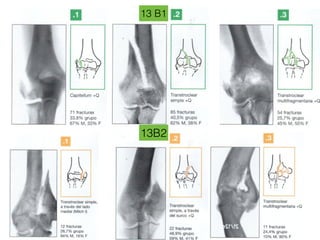

13 B1

13B2